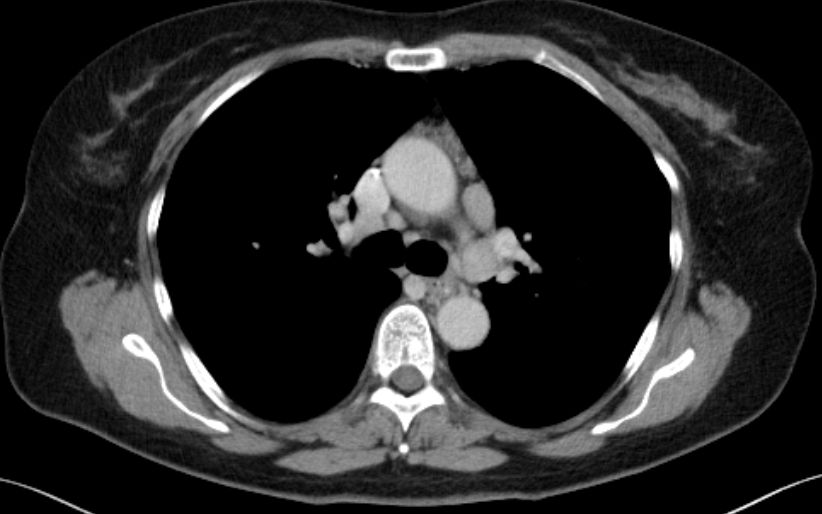

| Hilus- Lymphknoten | oft bihiläre Lymphadenopathie | 57-jährige Frau, die vor 15 Jahren ein Rektumkarzinom und vor einem Jahr ein Coecumkarzinom T4 N2b(14/14) Mo hatte. Beim Restaging vergrößerte Lymphknoten mediastinal, hilär beiderseits und paraaortal. Biopsie: floride Sarkoidose.![]() | |||||||||||||||||||||||||||||||||||||||||

| Lungen | mediastinale Lymphadenopathie | In 70% Lungeninterstitium befallen | Folge: Lungenfibrose. | ||||||||||||||||||||||||||||||||||||||||